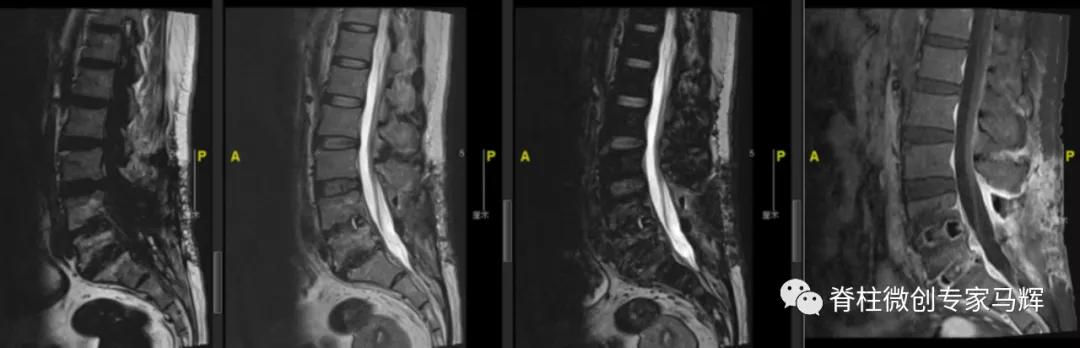

2018年腰椎术前

2018年腰椎术后

2019年腰椎内固定取出后